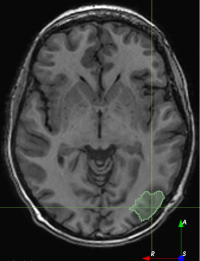

We evaluated the ability of semi-supervised learning to improve model performance by generating pseudo-labels for all unlabeled postoperative images in EPISURG (297). Pseudo-labels were generated by inferring the resection cavity label using the model trained on PubFull and EpiPre. The pseudo-labels and corresponding postoperative images were combined to create the Pseudo dataset.

We trained a model using PubFull, EpiPre and Pseudo (2371 images), obtaining a DSC of 81.7 (14.2). Adding the pseudo-labels to PubFull and EpiPre did not significantly improve performance (p=0.176𝑝0.176p=0.176), indicating our semi-supervised learning approach provided no advantage. Predictions from this model are shown in Fig. 3.